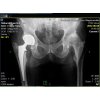

Csípőrisza

Csípőprotézis előtt állóknak a "receptre felírt" népszerű kisokos.

Hasznos információkkal a felkészülésről a kórházi 3-4 napról, és a rehabilitációról.